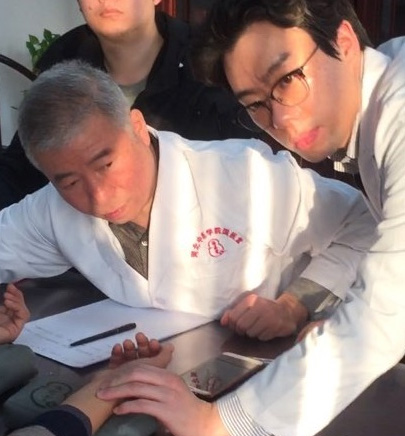

이사무 선생의 진료실에서

이사무 선생의 진료실에서